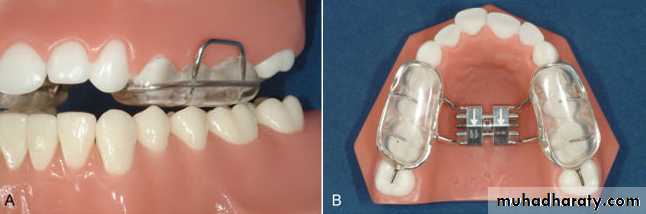

Palatal expansion can be achieved with slow activation using either of the following appliances:

• Split-plate removable appliance with expansion screw. However, it depends on patient compliance and treatment can take long time.

• Lingual arch either of W arch or quad helix design.

Both produce slow expansion and deliver a force of few hundreds grams and produce both skeletal and dental expansion.Expansion of narrow maxilla in late mixed dentition

• Split-plate removable appliance with expansion screw, this type depends on patient compliance and the treatment is longer.

The preferred appliance is adjustable lingual arch that is banded to molars and requires little patient cooperation.